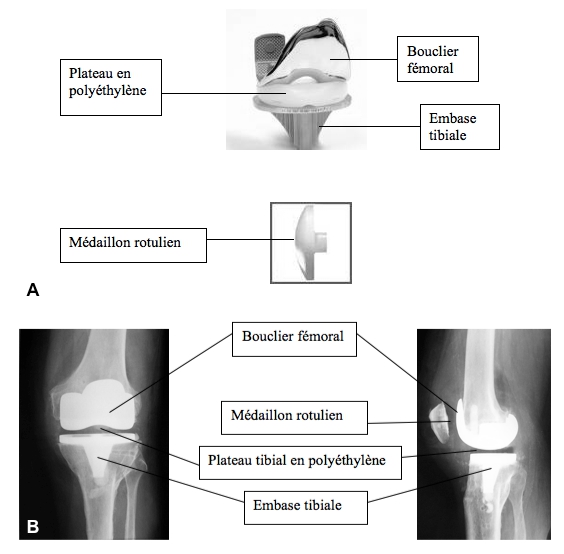

Figure 3 : A. Différents composants d'une prothèse totale du genou. B. Correspondance radiographique.

Une incision est faite à la partie antérieure du genou. A l’aide de matériel spécifique, le chirurgien retire l’ensemble du cartilage endommagé et les remplace par des surfaces métalliques au femur et au tibia (Figure 3A-B). Entre les deux surfaces métalliques, un implant en plastique est mis en place. Pour fixer les pièces métalliques dans l’os, du ciment acrylique associé à des antibiotiques est utilisé.